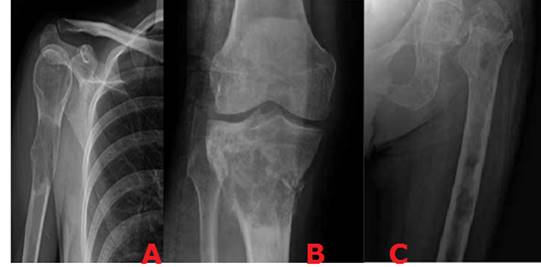

Reacción perióstica

Representa el extenso compromiso de la región cortical por el tumor o su anillo reactivo. La reacción perióstica puede ser positiva en donde el periostio se eleva por formación de nuevo hueso o puede ser negativa, cuando existe reabsorción del hueso como en el caso en la reabsorción subperióstica, en el hiperparatiroidismo. Existen varios tipos de reacción perióstica que incluyen: sólida o unilaminada, multilaminada o en cebolla, en sol naciente y el triángulo de Codman. La interrupción del periostio en las formas multi o unilaminadas sugieren procesos agresivos que rompen el periostio (Figura 4). 22